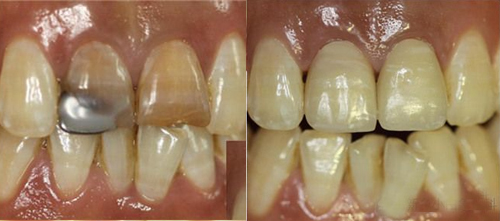

一患者上颌切牙外伤,在外院修复后因变色影响美观,来我院要求重新修复。X线检查发现根充不完善。经植入纤维桩、排龈后恢复牙冠外形、精修肩台、抛光牙体等后,更换新烤瓷牙。经过治疗后的牙齿,分辨不出真、假,患者非常满意。

治疗前后对比